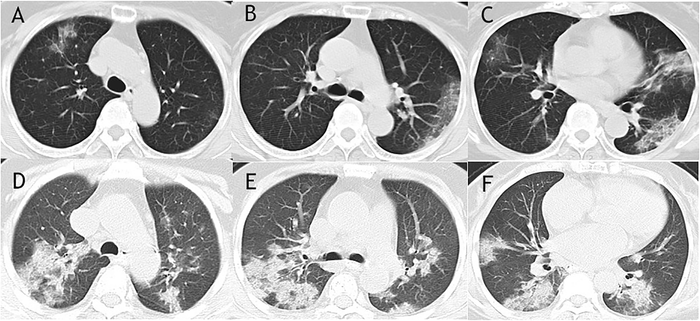

Figure 1 Imaging Changes In Severe Covid 19 Pneumonia Springerlink